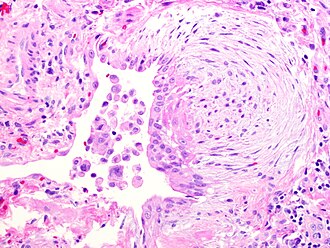

Fibroblast focus in usual interstitial pneumonia. H&E stain. | |

- Fibroblast foci:

- Interstitial inflammation.

- Spatial heterogeneity - patchy lesional distribution (areas of abnormal and normal lung may appear beside one another).

- Temporal heterogeneity - lesions of differing age side-by-side.[9]